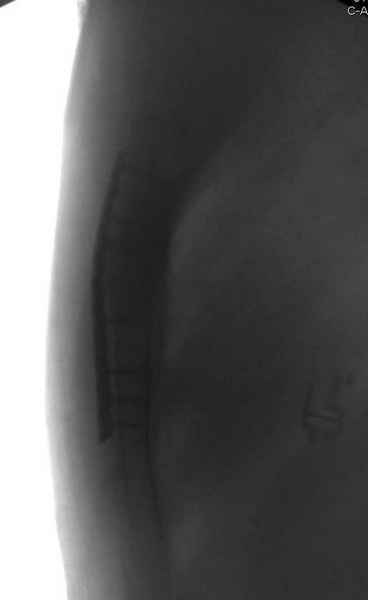

Юра, интересно, насколько такой остеосинтез контролирует степень репозиции, а то у меня имеются снимки девочки 11 лет, направленной ко мне на консультацию из одной из республик бывшего союза.

После торакальной операции, по-видимому, сильно натянули проволоку, и в результате получился захлест отломков в друг друга.

Оперировавший хирург предлагает подождать, а родителей беспокоит проблема прогрессирующей ассиметрии лица, как при кривошее.